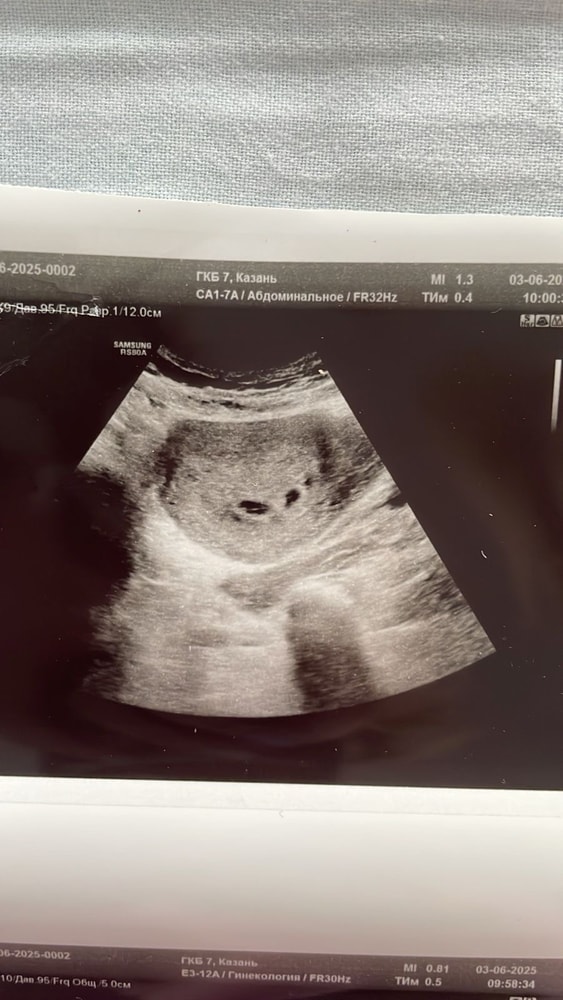

Лариса , как только датчик засунула,врач сразу сказала,а вы знаете что у вас 2 пя,я говорю нет. Потом стала сомневаться,я спросила а это может быть гематома,она сказала,что 100% не гематома,так как внутри нет жидкости,то есть крови. Я говорю,а почему один очерченный,а другой нет. Она сказал,что возможно один может просто отставать в развитии. И назначила контрольное узи через неделю

Евгения, в двух местах была на узи сегодня,нигде не сказали про гематому

Вот узи с перво клиники